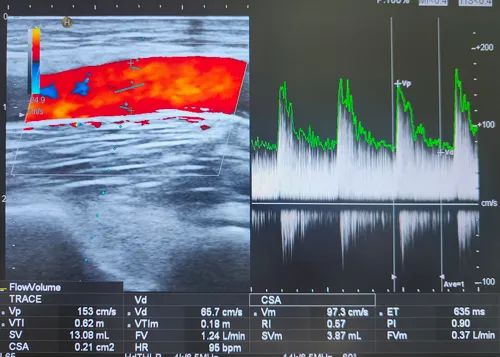

在(DSA)介入引導(dǎo)下

送球囊至血管狹窄處

用壓力泵對球囊加壓

將血管閉塞部位成功打開

較為狹窄處的血管

內(nèi)徑僅為1mm左右

術(shù)后

董阿姨內(nèi)瘺搏動及震顫明顯

通路恢復(fù)正常

當(dāng)日上機(jī)透析治療

血流量充盈滿足透析所需